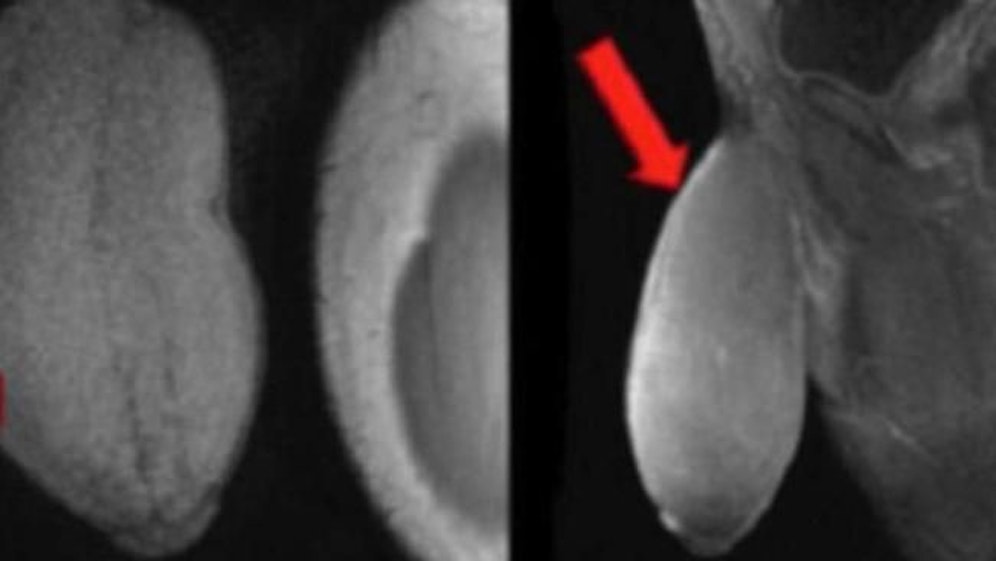

Sein Glied war ursprünglich 18 Zentimeter groß, im unerrigierten Zustand, und hatte die Form eines Footballs. Der Bursch litt sehr darunter, nicht nur Sport sondern auch Sex waren aufgrund der Größe seines Penis' unmöglich. Immer wieder bekam er spontane Erektionen, was zu zusätzlichen Problemen führte.

Das Ergebnis kann sich jetzt sehen lassen: Angeblich ist der Penis nun "ein wenig länger und dicker als der Durchschnitt". "Er sieht symmetrisch aus und der Patient war begeistert."